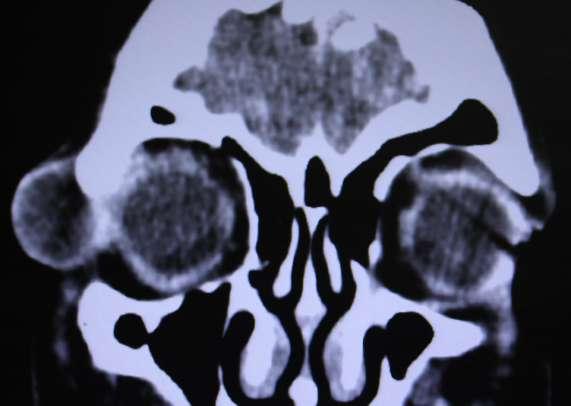

2.C. TUMOR DE CUERPO CAROTÍDEO + OCLUSIÓN DE RAMA ARTERIAL

TAC (imagen B): Tumor de cuerpo carotídeo derecho, shamblin III

A B

RETINAL CON ISQUEMIA MACULAR OD

Caso aportado por Dr. Cristian Sánchez

Clínica:

AV: OD CAE =0,2 / OI 0,8

PIO: OD 10/ OI: 16

BMC: Polo anterior normal

FO: Oclusión de la arteria ciliorretinal con isquemia macular OD

Obstrucción de la arteria ciliorretinal (OACR)

ü La arteria ciliorretiniana esta presente en 15-30% de los ojos

ü Es rama de arterias ciliares cortas posteriores

ü La etiología de la OACR suele estar relacionada con enfermedad carotídea u otros procesos tromboembólicos relacionados con estados de hipercoagulabilidad y autoinmunidad.

ü El diagnóstico suele ser fundoscópico con la visualización en nuestro caso del área retineana isquémica en el terrirotio de la arteria ciliorretineana y la visualización del embolo.